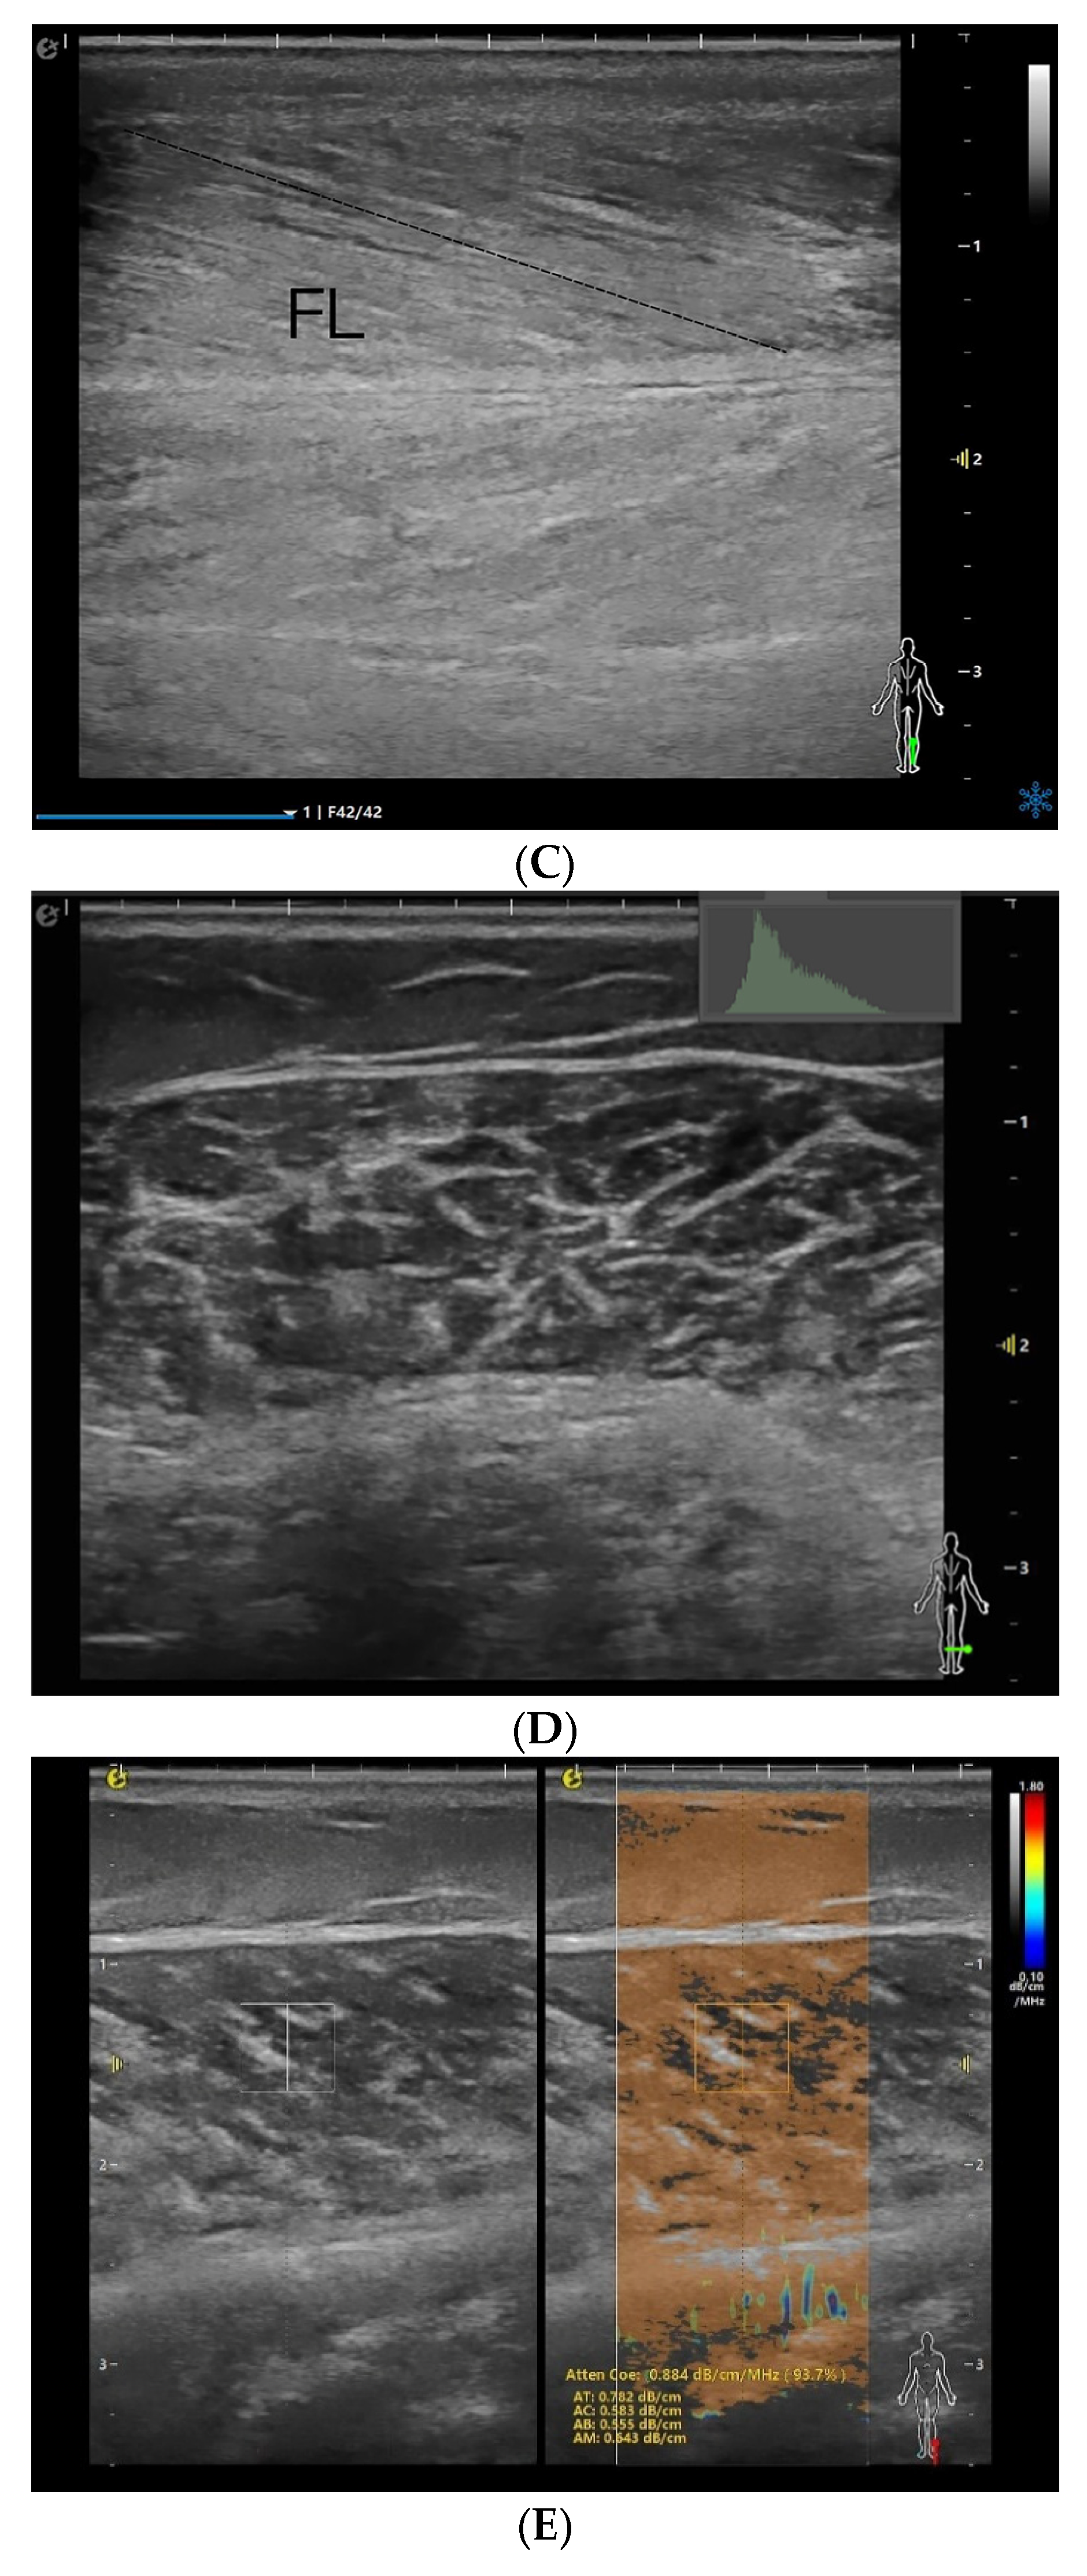

The patients were placed in the prone position, with the ankle joint placed outside the examination bed. The probe was placed on top of the skin with minimal load to ensure that no external pressure could affect the tests. The musculoskeletal mode was selected, and the right medial head of the gastrocnemius was viewed in the upper middle 1/3 of the line from the medial tibial condyle to the highest point of the medial malleolus [17]. The probe was parallel to the long axis of the gastrocnemius muscle, and MT, PA, and FL were measured in a relaxed state (Figure 1A–C). The two-dimensional cross-sectional images were imported into Adobe Photoshop 23, and the EI was measured (Figure 1D). Because pixel intensity is sensitive to time gain compensation (TGC), a dedicated “Muscle-Sarcopenia” preset was created and locked before patient enrolment. Total gain was fixed at 72 dB; TGC sliders were set to the factory linear curve. Dynamic range (60 dB), frequency (12 MHz), depth (3 cm) and single focal zone (1.5 cm) were identical for every scan. EI was quantified by placing a 10 × 5 mm ROI between the aponeuroses; the mean gray value (0–255) was used for analysis.

Figure 1.

MT (A), PA (B), FL (C), EI (D), and Atten Coe (E) of the medial head of the right gastrocnemius muscle in the relaxed state. MT = muscle thickness (mm); PA = pinna angle (°); FL = fascicle length (mm); Atten Coe = attenuation coefficient (dB/cm/MHz); EI = echo intensity.